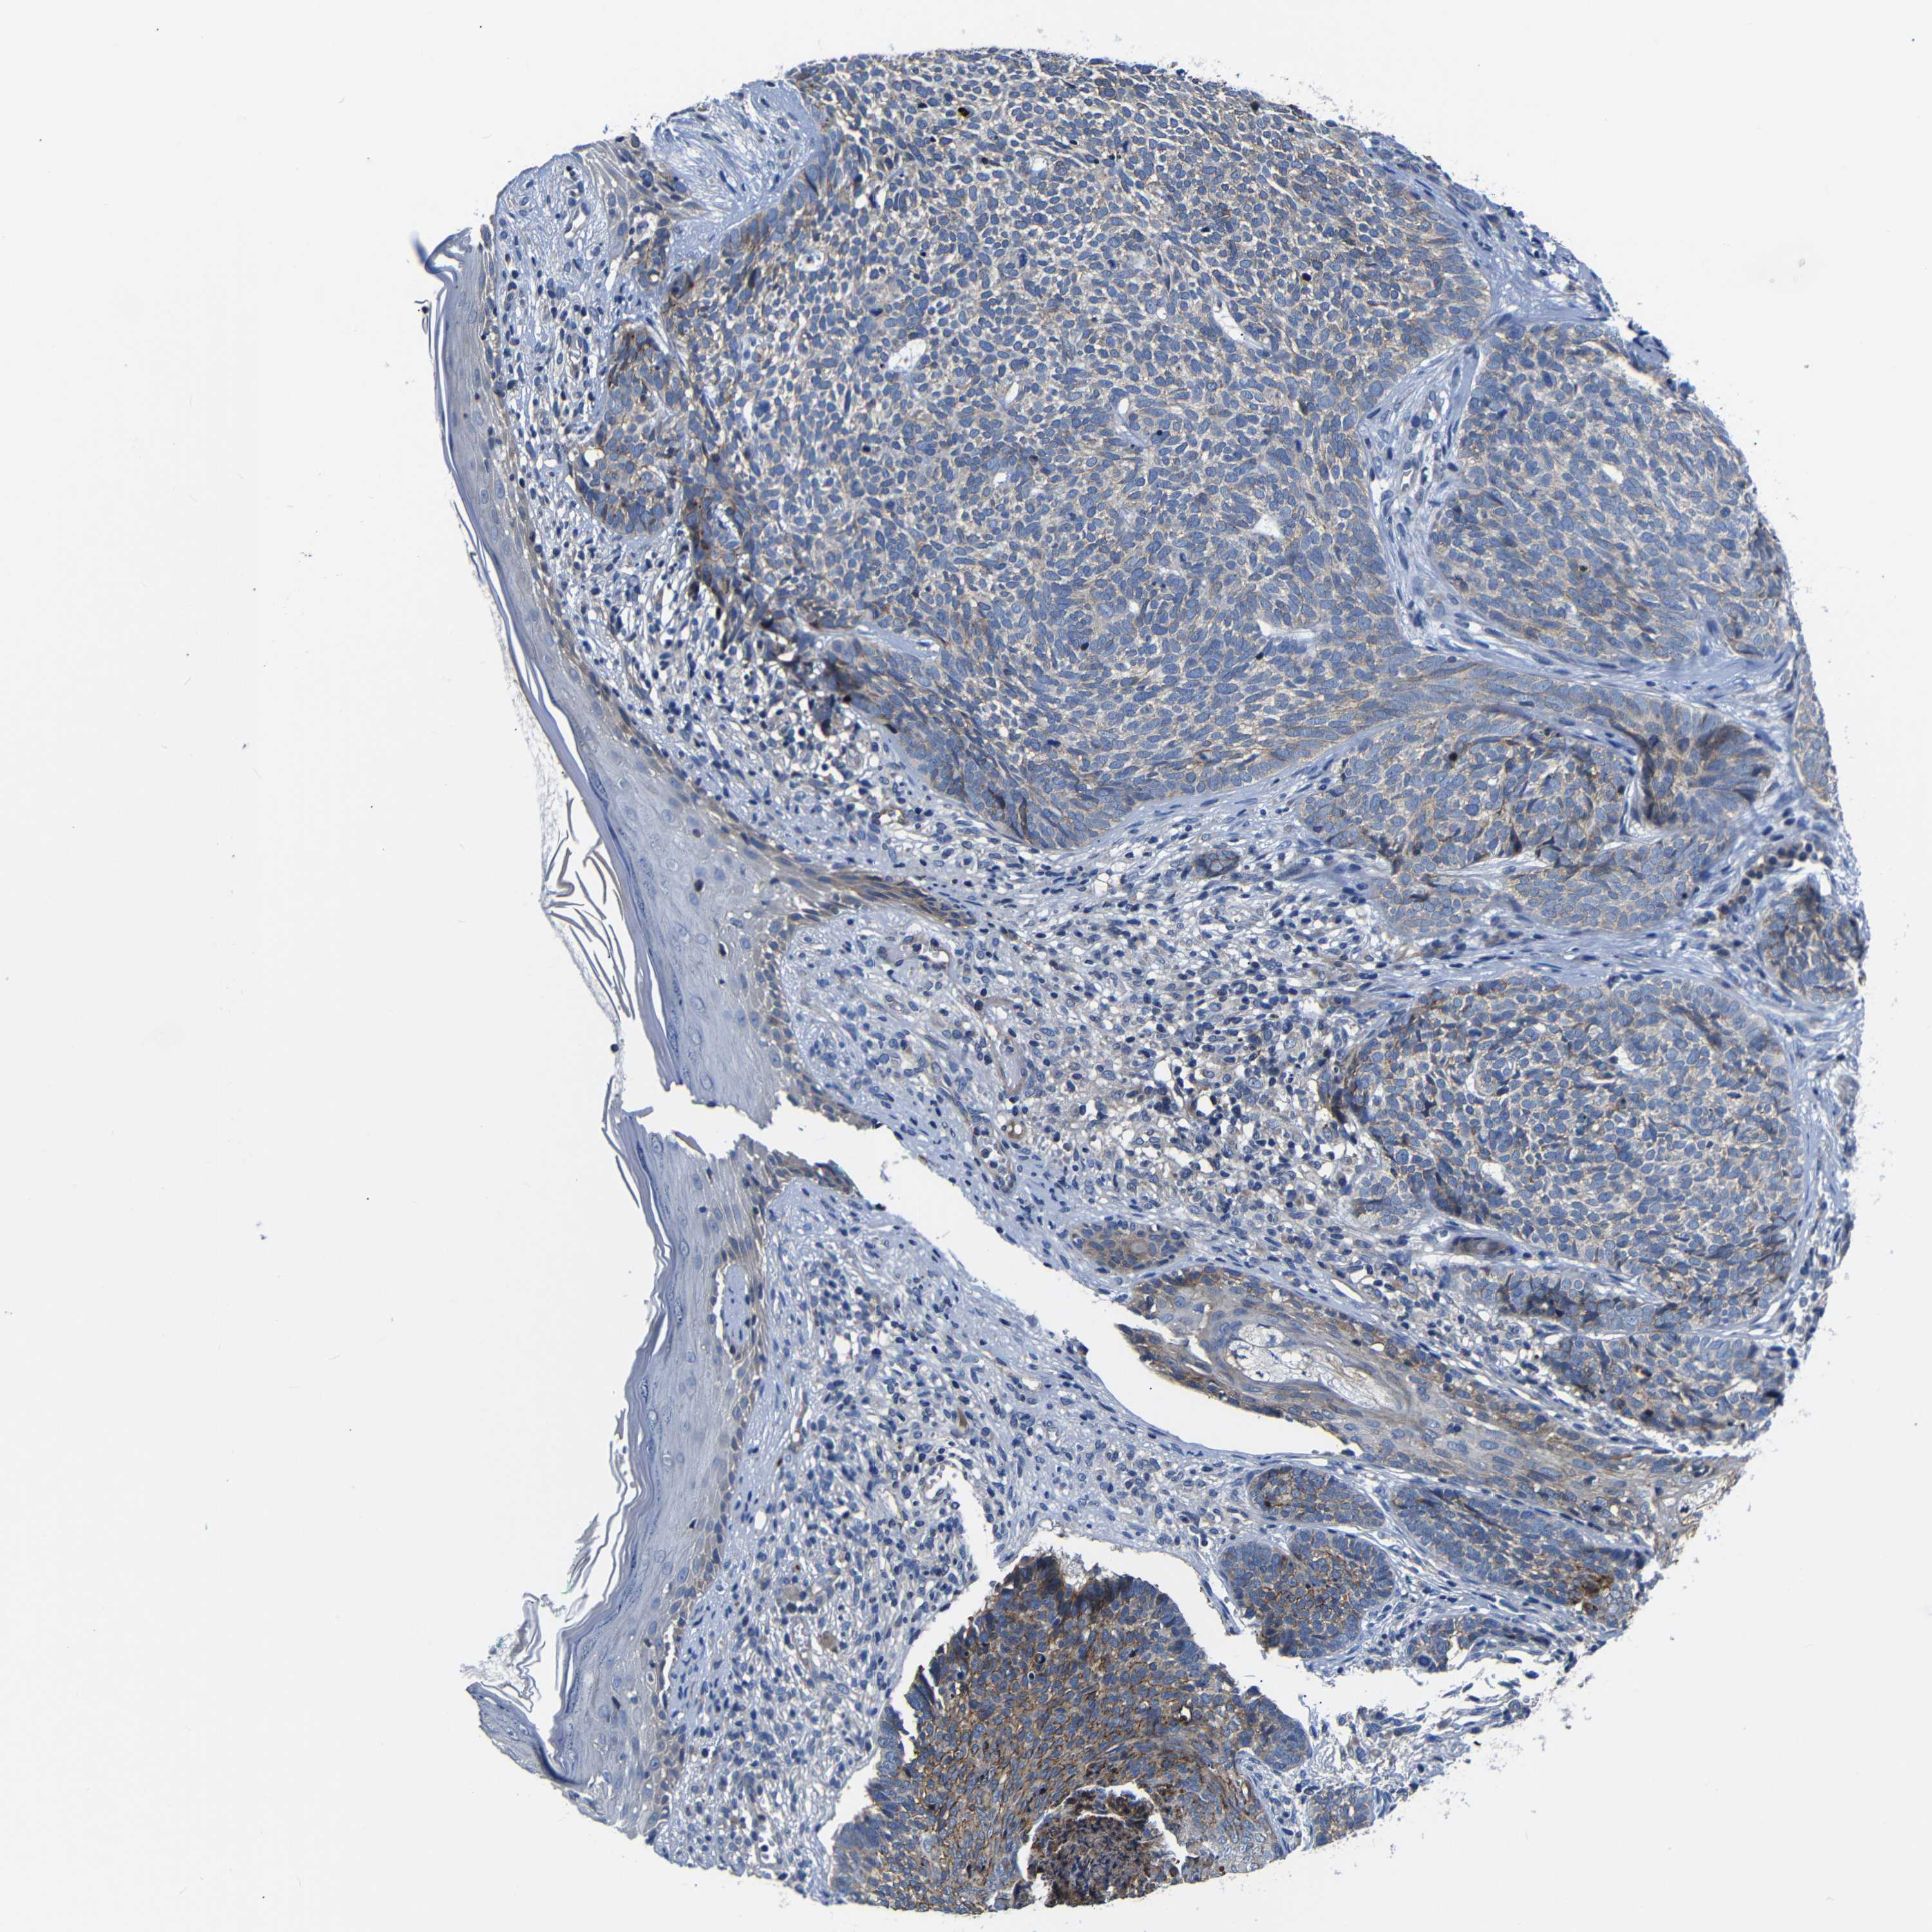

SKIN CANCER - Protein expressioni

A mouse-over function shows sample information and annotation data. Click on an image to view it in a full screen mode. Samples can be filtered based on level of antibody staining by selecting one or several of the following categories: high, medium, low and not detected. The assay and annotation is described here.

Each image is clickable and will lead to virtual microscopy that enables deeper exploration of all samples and also displays staining intensity scores, fraction scores and subcellular localization as well as patient and tissue information for each sample.

HPA030212

HPA030213

HPA030214

HPA030215

CAB013496

Basal cell carcinoma

Squamous cell carcinoma, NOS

Squamous cell carcinoma, metastatic, NOS

Adnexal tumor, benign